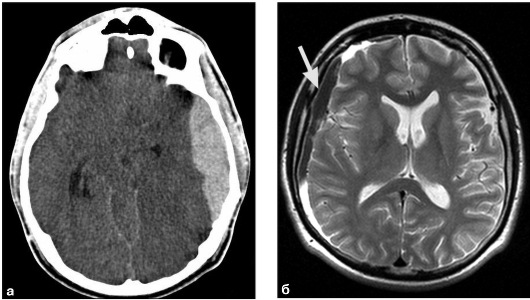

На снимке отек мозга:

Вследствие гематомы: а. На КТ; Б. На МРТ.

Из-за накопления жидкости в тканях мозга, происходит давление внутри, возникает отек.